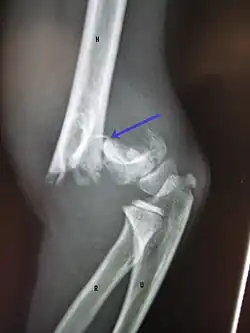

Anterior humeral line - It is a line drawn down along the front of the humerus on the lateral view and it should pass through the middle third of the capitulum of the humerus.[9] If it passes through the anterior third of the capitulum, it indicates the posterior displacement of distal fragment.[8]

Fat pad sign/sail sign - A non-displaced fracture can be difficult to identify and a fracture line may not be visible on the X-rays. However, the presence of a joint effusion is helpful in identifying a non-displaced fracture. Bleeding from the fracture expands the joint capsule and is visualized on the lateral view as a darker area anteriorly and posteriorly, and is known as the sail sign.[8]

Coronoid line - A line drawn along the anterior border of the coronoid process of the ulna should touch the anterior part of the lateral condyle of the humerus. If lateral condyle appears posterior to this line, it indicates the posterior displacement of lateral condyle.[8]